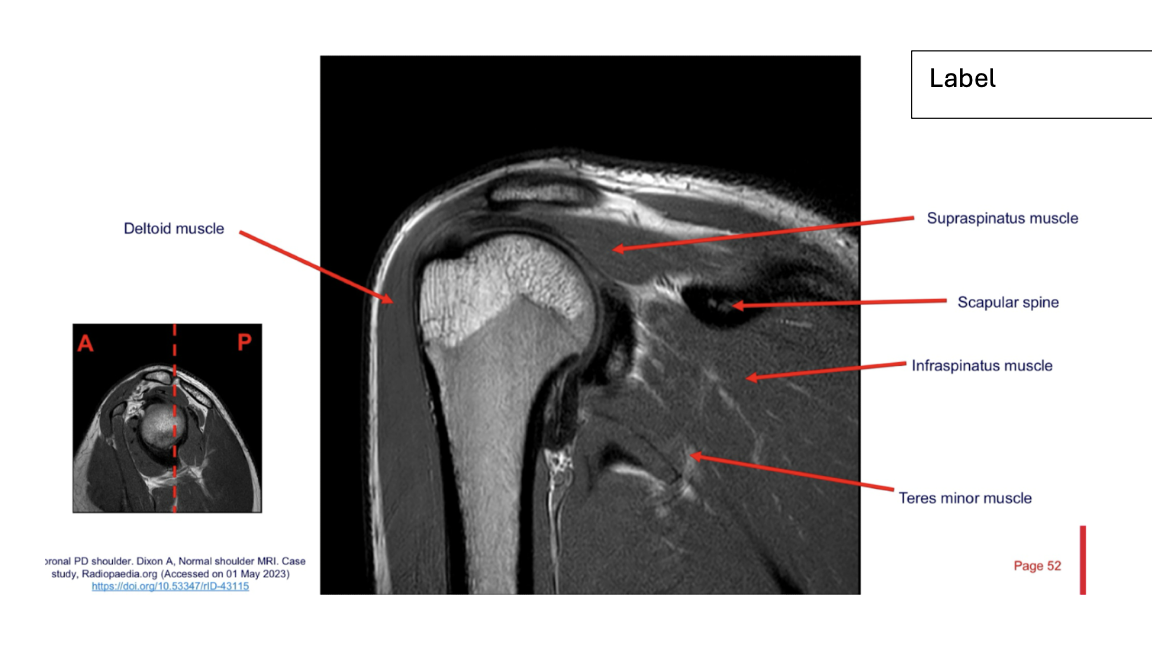

Sequence + Why?

PD- proton density

• Fat is bright, fluid is bright, intermediate signal from muscle.